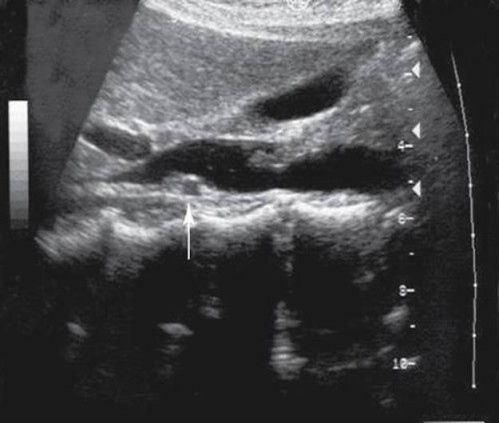

The arrow is demonstrating which of the following vascular structures?

right renal artery